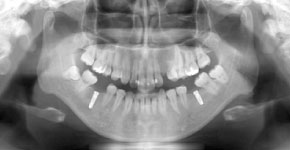

パノラマレントゲン(2D)撮影

低被ばくで、広い範囲の撮影が可能なCT(3D撮影)機器です。デジタル方式ですので、被ばく量が従来のものと比べ各段に軽減されています。

3D撮影ができることにより、多角的な診断が可能となり、インプラント治療などにおける診断をはじめ、複雑な治療である親知らずの抜歯や根管治療を安全に、且つより正確に行うことが可能です。